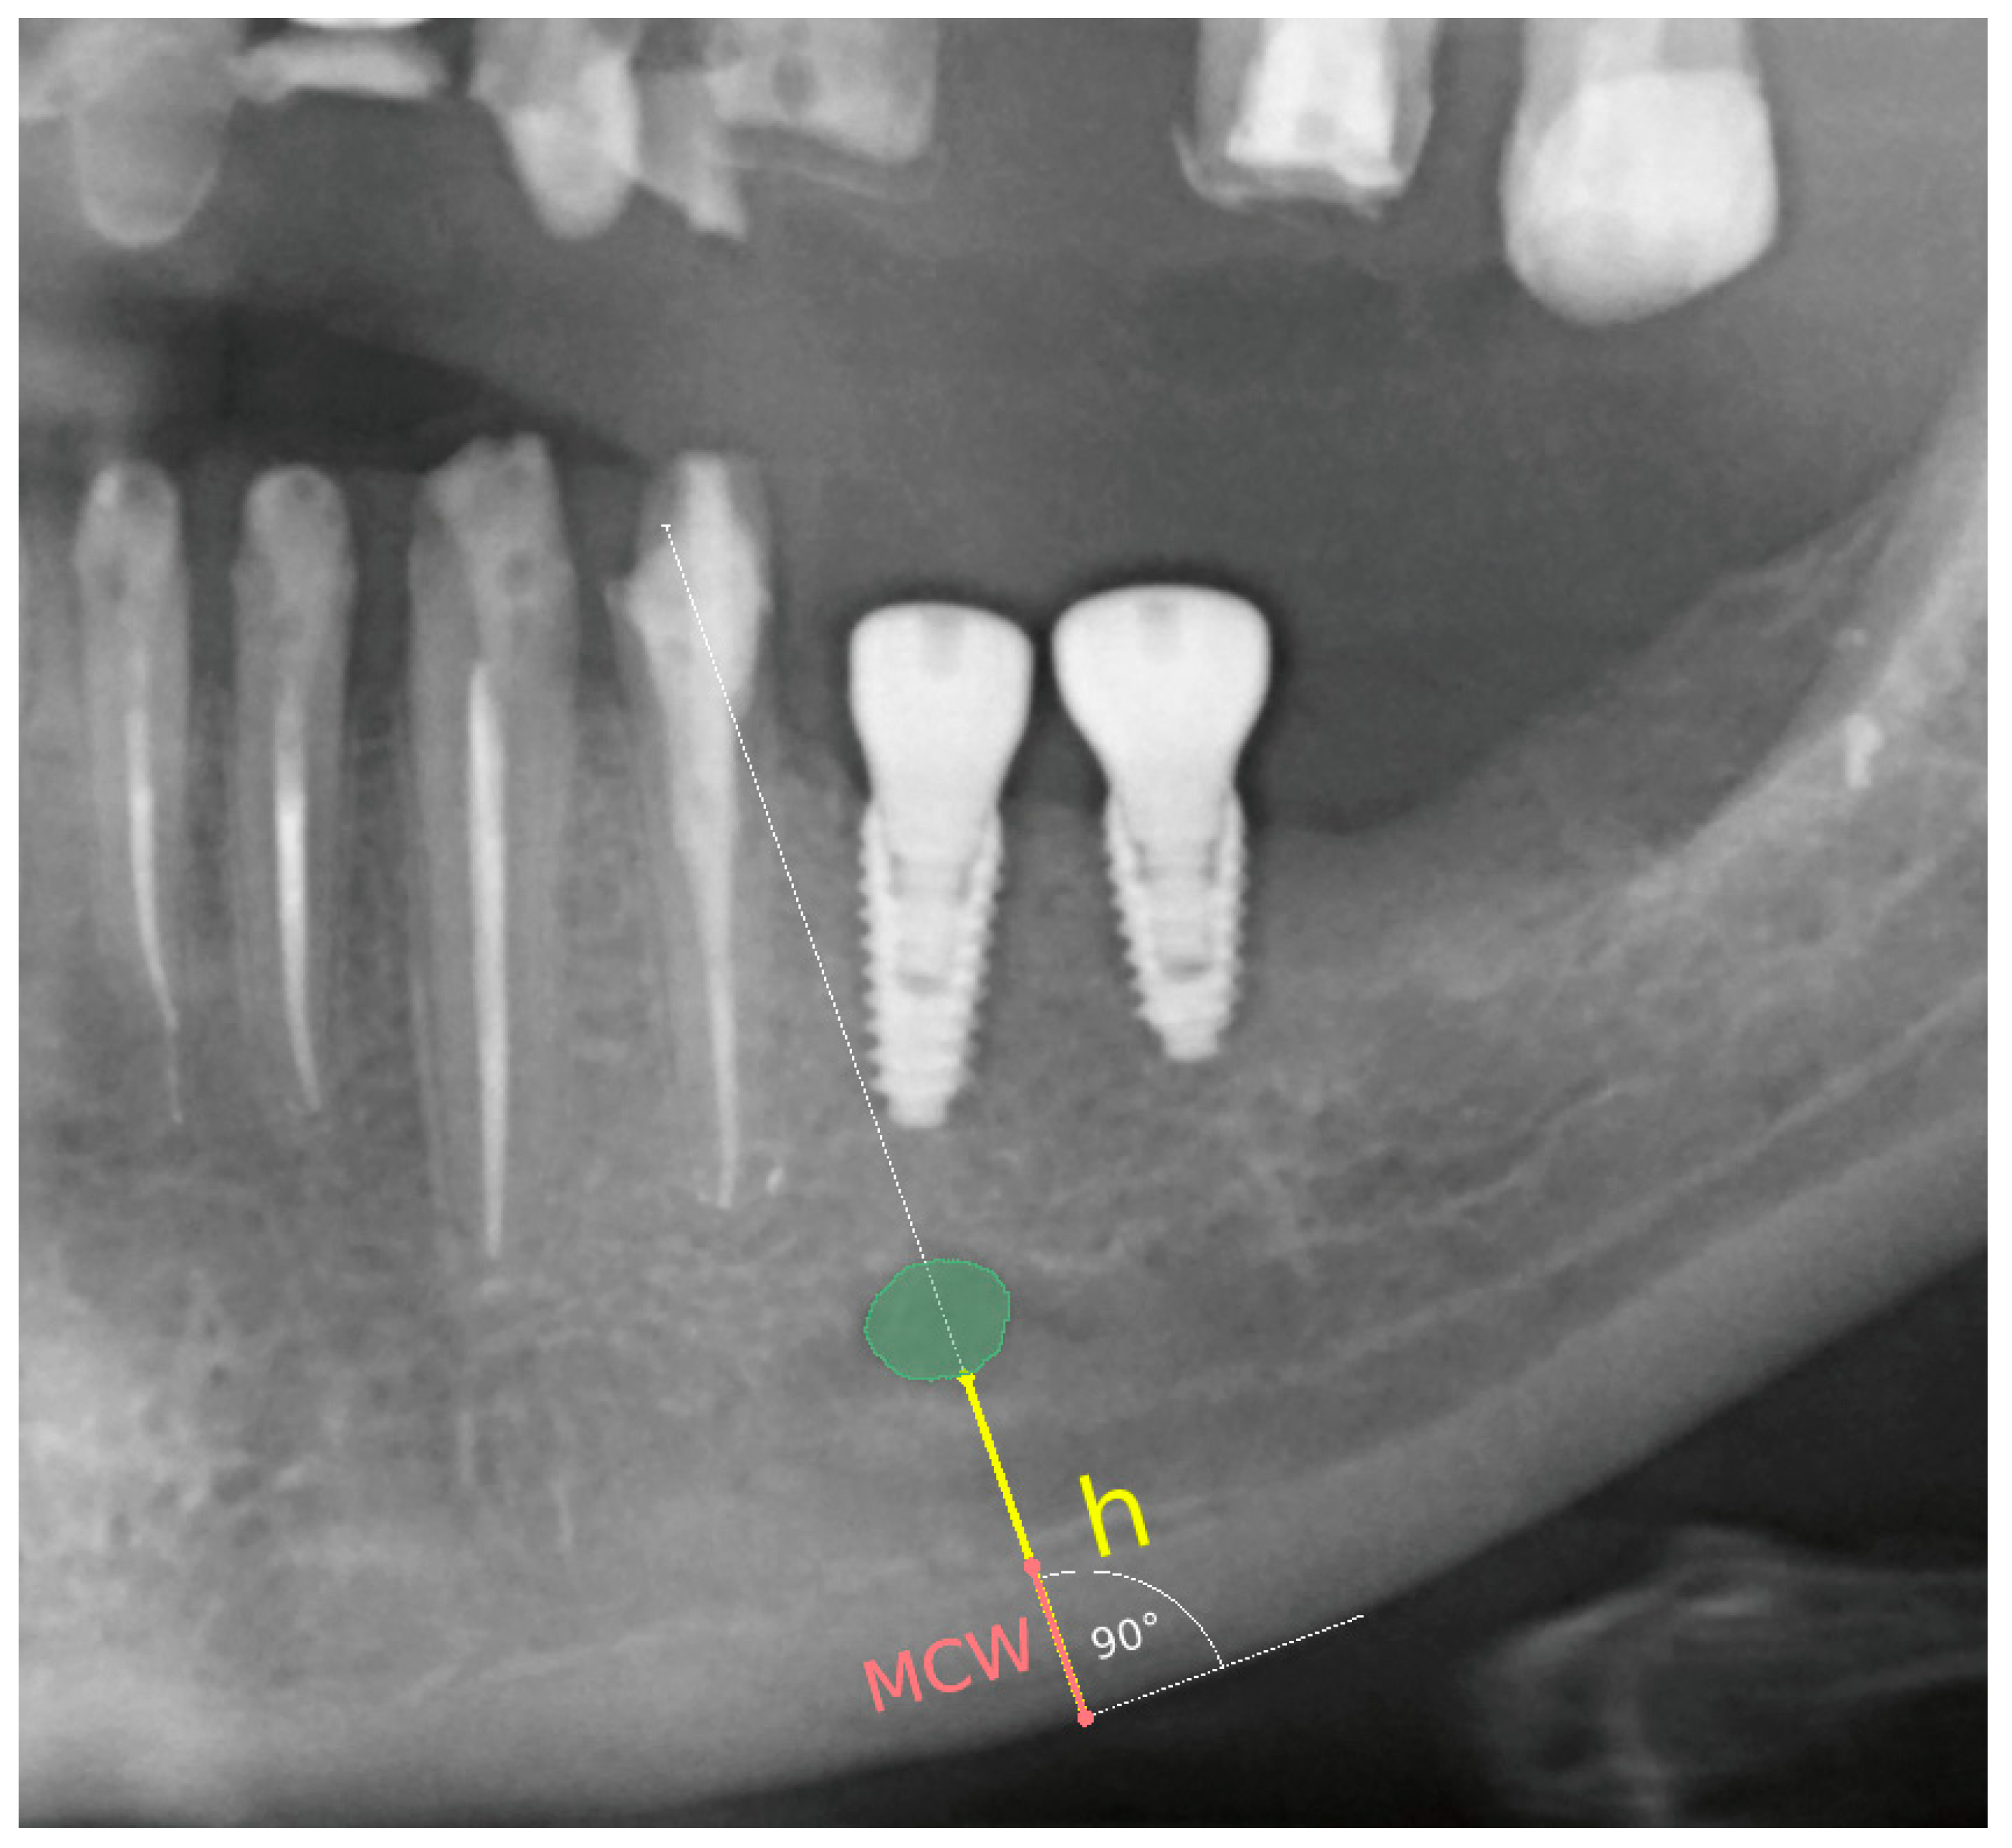

The following radiomorphometric measurements were taken on each radiograph (Figure 2):

Figure 2. Demonstration of the technique for measuring the compact bone thickness of the mandible and the distance between the mental foramen and the lower border of the mandibular compact bone on pantomographic images using the 3D Slicer software version 4.8.1.

A line was established along the lower border of the mandible, and a perpendicular line through the center of the mental foramen was drawn.

Distance between the mental foramen and the lower border of the mandibular cortical bone (h) was measured.

Mandibular cortical width in the chin region (MCW): Thickness of the mandibular cortical bone, measured along a line perpendicular to the lower portion of the mandible through the center of the mental foramen, was determined. A value greater than 3.1 mm was considered normal [26].

Based on these measurements, the panoramic mandibular index (PMI) was calculated. The panoramic mandibular index (PMI) was computed as the ratio of MCW/h [27]. PMI was calculated as the ratio of the thickness of the mandibular corpus compact bone (MCW) to the height measured from the lower border of the mandible to the lower edge of the mental foramen (h). A value greater than 0.3 is considered the norm [28,29].

P M I = M C W h

The MCW measurement was obtained by drawing a line tangential to the lower border of the mandible and a second line perpendicular to this tangent intersecting the lower border of the mandible and the mental foramen, along which the thickness of the mandibular cortex was measured.